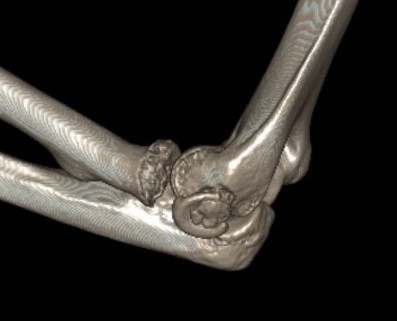

Type 3: Severely comminuted fracture / Non reconstructable

Type 3 radial head fractures

3. Essex Lopresti

Fracture radial head + disruption interosseous membrane + dorsal dislocation of DRUJ

Radial Head Arthroplasty (RHA)

Design

Cobalt chrome / pyrocarbon / titanium

Modular - various head diameter / thickness + various stem sizes + collars to build up radial neck if required

Fixation - press fit v loose fit